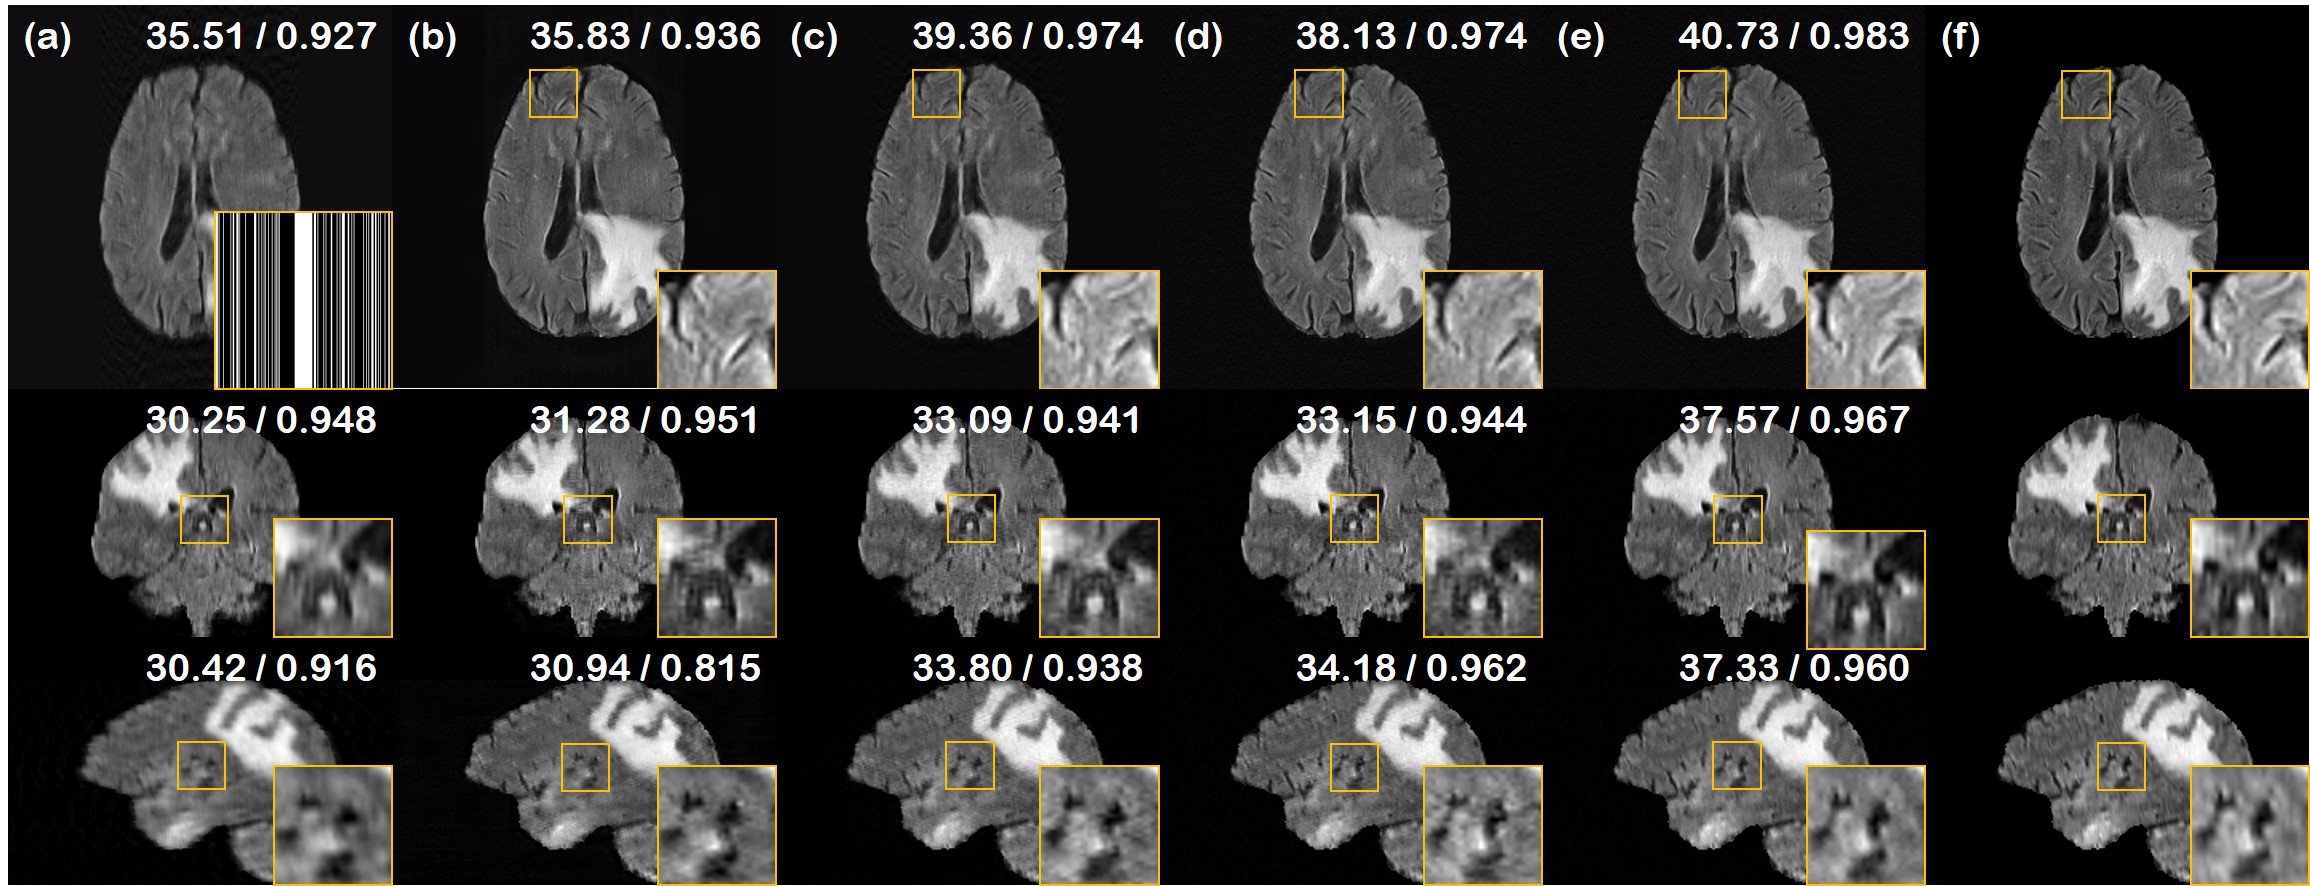

Refer to caption

Figure 8: CS-MRI results of the test data (First row: axial slice, second row: sagittal slice, third row: coronal slice). (a) zero-filled, (b) U-Net [36], (c) DuDoRNet [38], (d) Score-MRI [7], (e) proposed method, (f) ground truth. PSNR/SSIM values presented in the upper right corner. Mask presented in the first row of (a): Sub-sampling mask applied to all slices.

We test our method on the reconstruction of 1D uniform random sub-sampled images, as was used in [36]. Specifically, we keep 15% of the autocalibrating signal (ACS) region in the center, and retain only the half of the k-space sampling lines, corresponding to approximately 2×\times acceleration factor for the acquisition scheme. The results are presented in Table 3 and supplementary Fig. 8. Consistent with what was observed in the experiments with SV-CT and LA-CT, we observe large improvements over the prior arts.